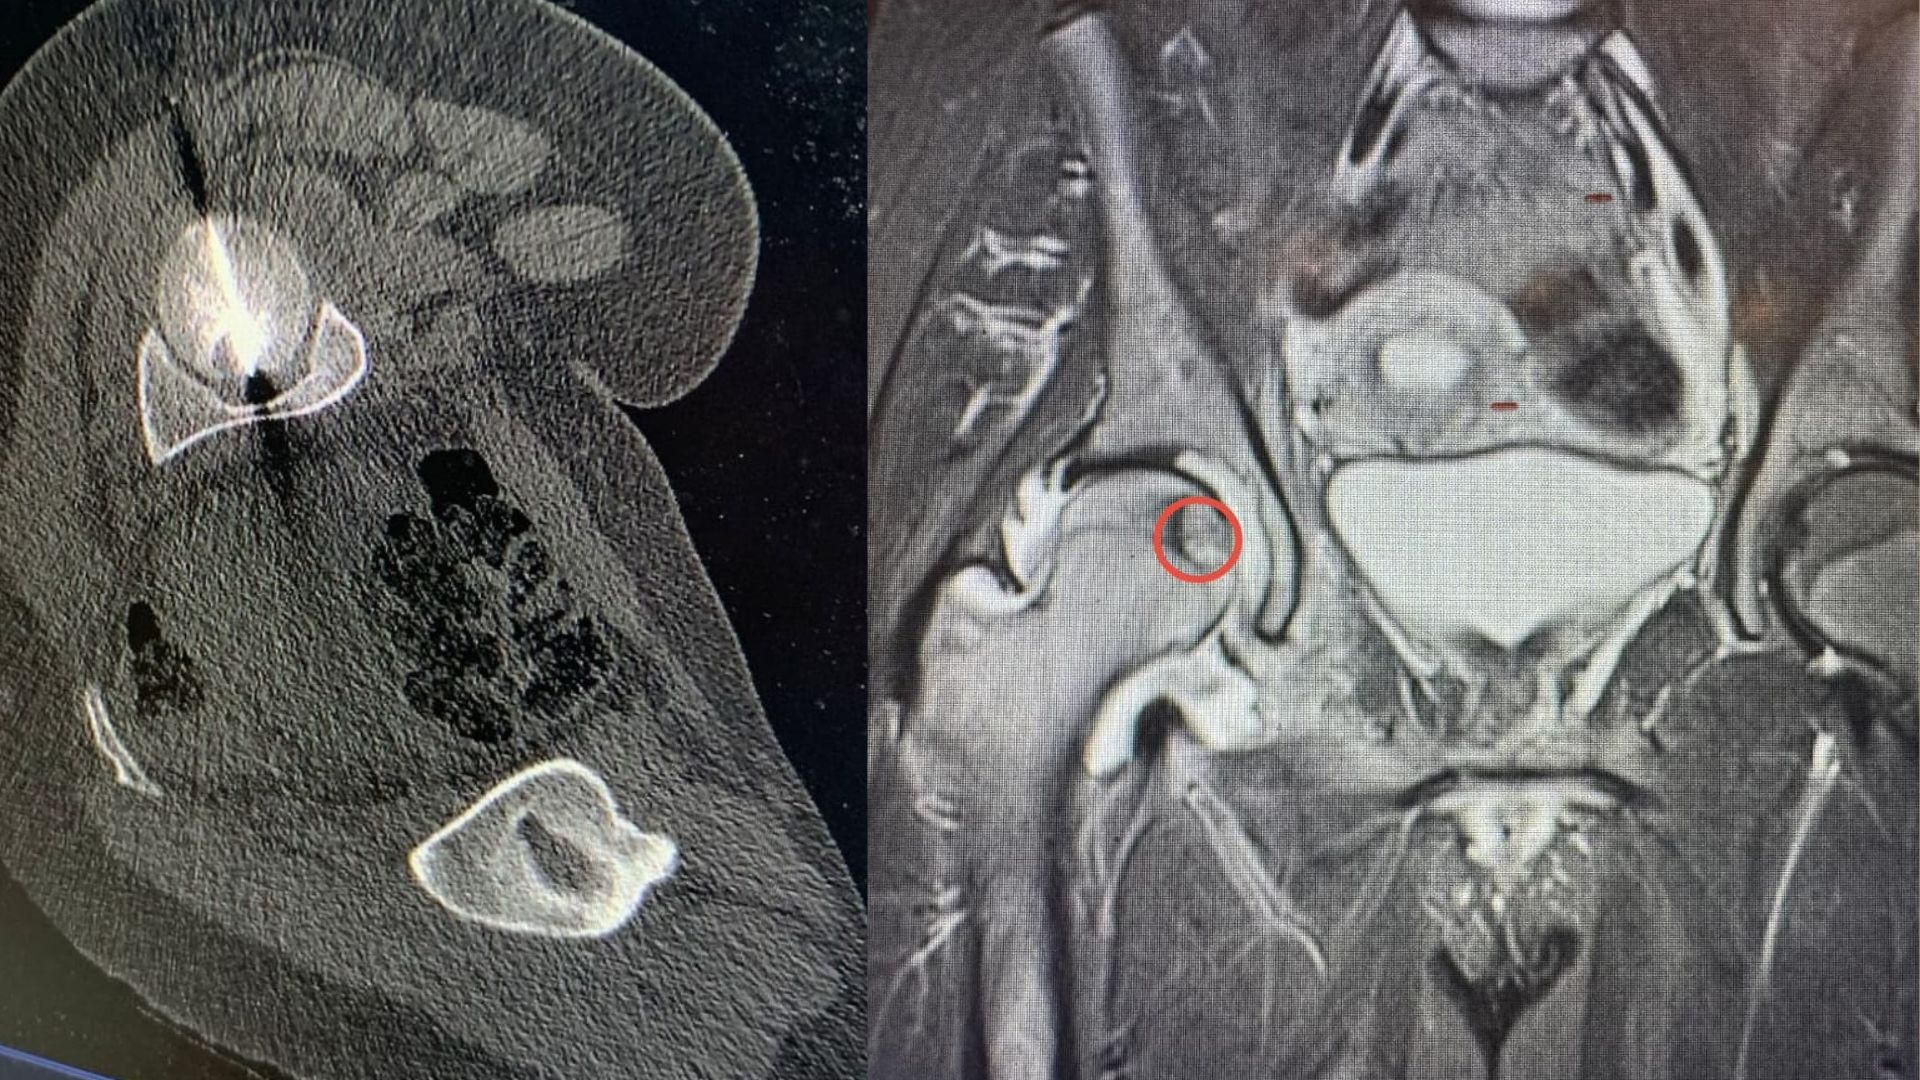

أعلن مستشفى الجامعة الأردنية عن إجراء تدخل علاجي متقدم في قسم الأشعة، تمكن من خلاله فريق طبي متعدد الاختصاصات من معالجة ورم عظمي في رأس عظم الفخذ لمريض ثلاثيني، وهو موقع شديد الحساسية ويُعد من أكثر المواضع صعوبة في الوصول إليها جراحياً.

• الفريق الطبي نجح في الوصول إلى مركز الورم بدقة باستخدام التصوير الطبقي المحوري (CT Scan).

• تم إجراء الكي الحراري باستخدام تقنية المايكروويف، وهي من أحدث التقنيات العالمية لعلاج أورام العظام دون جراحة مفتوحة.